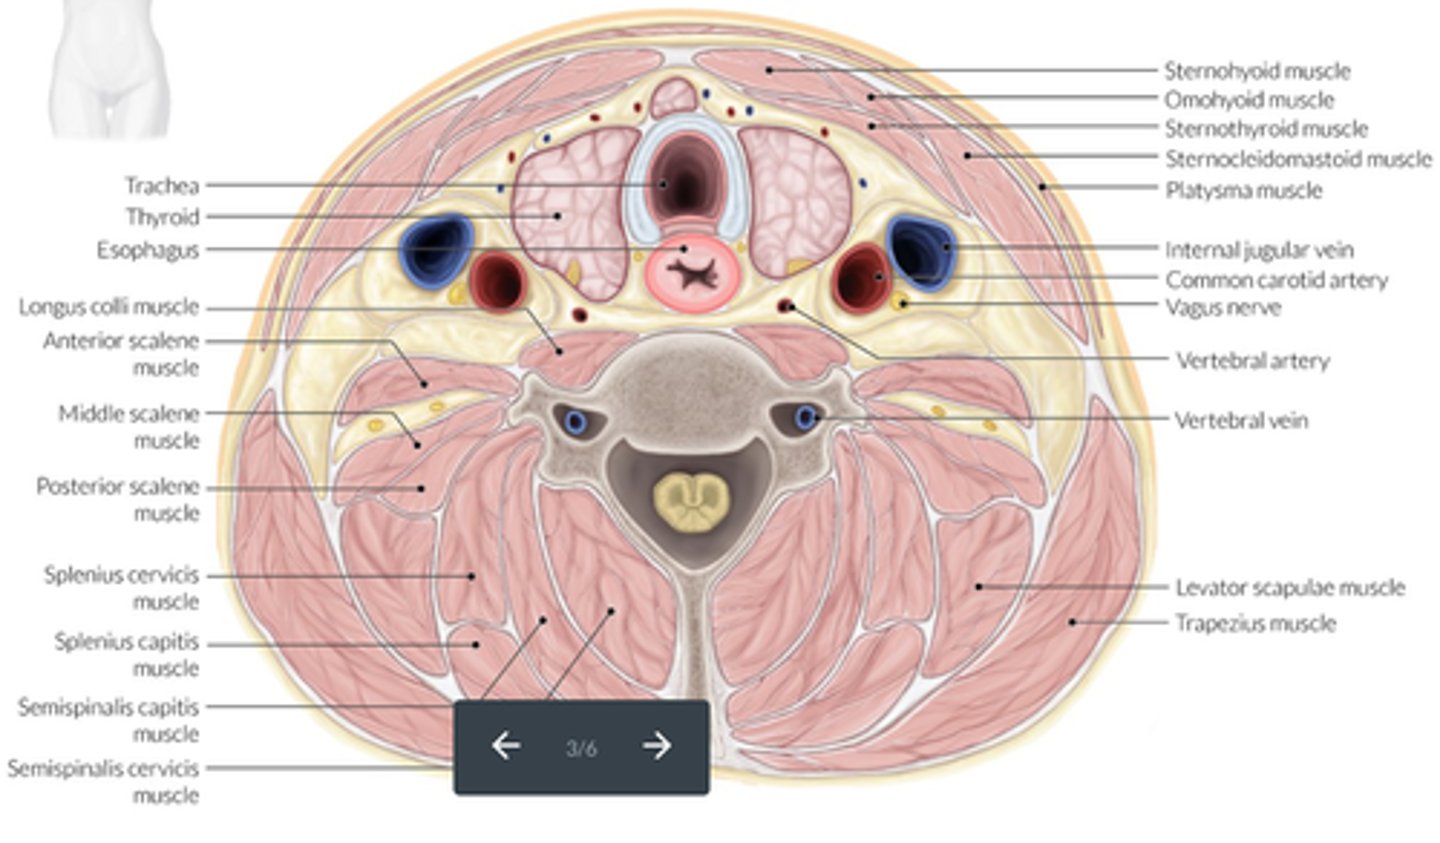

Muscles of the neck - Longus colli muscles:

-Located on the _____ surface of the vertebral column

-Lie adjacent to the ____ and _____ to the thyroid lobe and CCA

-May be mistaken for an enlarged _____

-Located on the anterior surface of the vertebral column

-Lie adjacent to the trachea and posterior to the thyroid lobe and CCA

-May be mistaken for an enlarged parathyroid gland

Muscles of the neck - Sternocleidomastoid Muscles:

-_____ and _____ neck muscles

-Located _____ to the thyroid lobes, sternohyoid muscle and sternothyroid muscle

-Lateral and superficial neck muscles

-Located lateral to the thyroid lobes, sternohyoid muscle and sternothyroid muscle

Muscles of the neck - Strap Muscles:

-A collective group of long flat neck muscles

-Located _____ and _____ to the thyroid gland

Include the:

-Sternothyroid - located directly _____ to the thyroid gland

-Omohyoid - located _____ to the sternothyroid muscles

-Sternohyoid - located _____ to the sternothyroid muscles

-Located anterior and lateral to the thyroid gland

-Sternothyroid - located directly superficial to the thyroid gland

-Omohyoid - located lateral to the sternothyroid muscles

-Sternohyoid - located anterior to the sternothyroid muscles

Location - Thyroid Lobes:

-_____ and _____ to the corresponding CCA and IJV

-_____ and _____ to the SCM and strap muscles

-_____ to the longus colli muscle

-_____ to the trachea and esophagus

-_____ to the thyroid cartilage of the larynx

-Medial and anterior to the corresponding CCA and IJV

-Posterior and medial to the SCM and strap muscles

-Anterior to the longus colli muscle

-Anterolateral to the trachea and esophagus

-Inferior to the thyroid cartilage of the larynx

Sonographic Appearance:

-Thyroid lobes and isthmus appear as ____geneous solid structures demonstrating a medium-gray echo pattern with a surrounding thin ____echoic line

-Sternocleidomastoid muscle are _____ and oval in shape appearing ____echoic compared with the normal thyroid gland

-Strap muscles are _____ and ____echoic compared with the normal thyroid gland

-Longus colli muscles appear ____echoic compared with the normal thyroid gland

-Thyroid lobes and isthmus appear as homogeneous solid structures demonstrating a medium-gray echo pattern with a surrounding thin hyperechoic line

-Sternocleidomastoid muscle are large and oval in shape appearing hypoechoic compared with the normal thyroid gland

-Strap muscles are thin and hypoechoic compared with the normal thyroid gland

-Longus colli muscles appear hypoechoic compared with the normal thyroid gland